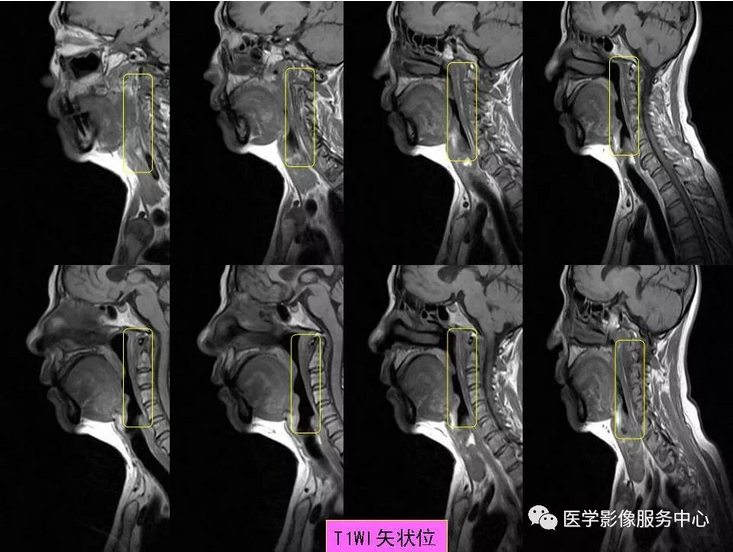

颈椎前缘的条状高信号影,终于知道是什么啦~~

颈项疼痛是临床常见症状,最常见的原因就是颈椎病,包括颈椎骨质增生,颈椎间孔狭窄、颈间盘膨隆突出等表现,综合运用DR、CT、MRI这些影像检查方法,比较容易做出诊断,除此之外,引起颈项疼痛,还有比较少见的原因,不为影像诊断及临床医师所熟知,接下来我们看看下面的2个病例,比较少见的颈长肌肌腱炎。

颈长肌肌腱炎,是以颈项疼痛为主要临床表现的一种疾病,因颈长肌前方毗邻食道及咽部,常常伴发咽部疼痛和吞咽疼痛,临床及影像科医生对其认识较少,常易与其它引起颈项疼痛的疾病混淆 。

其病因为羟磷灰石结晶沉积于颈长肌上斜肌引起的炎性反应,以刺激组织渗出为主。羟磷灰石结晶沉积机制尚不十分明确,可能与损伤、组织坏死和炎症等因素相关。